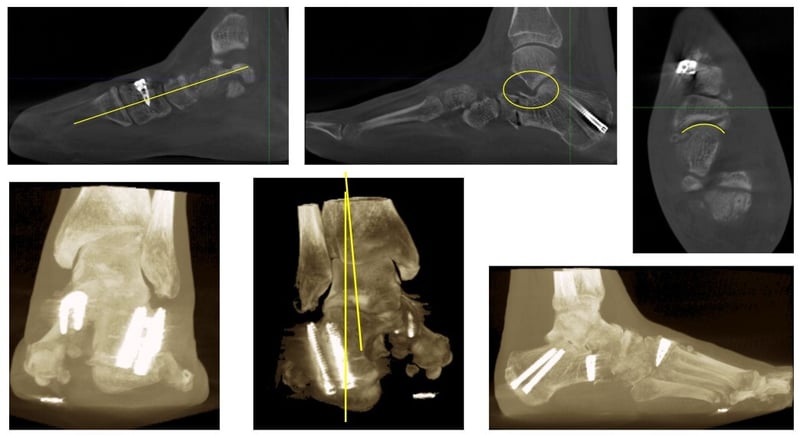

Tac in carico post-intervento, con assi di riferimento che mostrano la correzione delle deformità.

Chiudiamo menzionando che di recente è stato proposto anche nell’adulto l’utilizzo di tecniche chirurgiche efficaci per la correzione del piede pediatrico (calcagno stop ed endortesi).

- Nei casi in cui questo non sia più possibile, per la gravità della deformità sono necessari interventi di artrodesi, cioè fusione di una o più articolazioni, per ricreare la normale forma del piede e riportarlo in asse. Si tratta di interventi più importanti, ma con un alto tasso di soddisfazione da parte del paziente che può osservare, in maniera ancora più lampante rispetto ai precedenti interventi citati, il cambiamento nella forma dell’arto. Il mio team oggi li esegue senza incisioni e con soluzioni mini-invasive percutanee, avendo introdotto con affidabilità nella gestione delle grande deformità tecnologie simili a quelle impiegate per la correzione dell’alluce valgo mini-invasiva. Queste soluzioni mini-invasive non riducono i tempi di guarigione scheletrica piena che, in questi casi sono sempre di 3-4 mesi, ma riducono i rischi di complicanze, quali infezioni e ritardi di guarigione della cute, riducono l’esperienza del dolore post-operatorio e sono compatibili con un carico immediato nel post-operatorio.